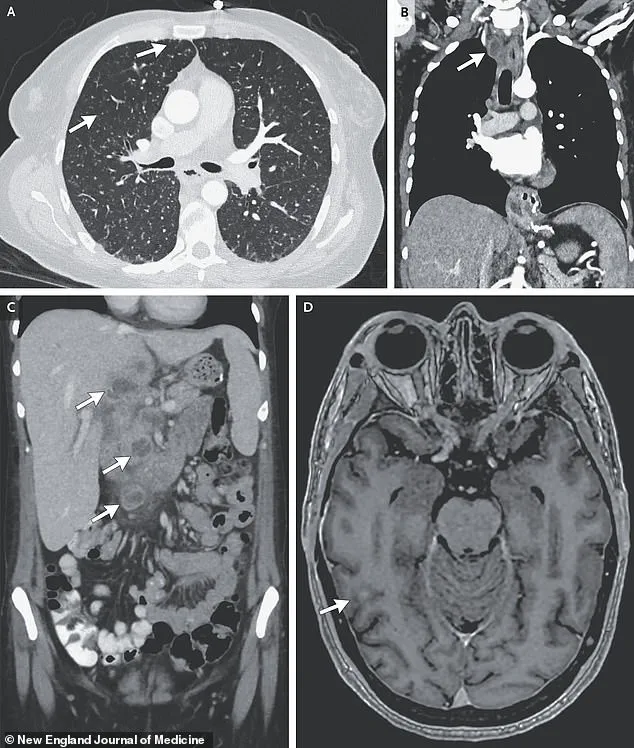

Further imaging and biopsies painted a more sinister picture.

Lesions were detected in her liver, lymph nodes, pancreas, and brain—organs that should have been untouched by the disease.

If left untreated, it can progress to severe respiratory failure, with the infection spreading to other organs, including the brain, liver, and lymph nodes.

In some cases, TB in the central nervous system can cause devastating neurological damage, leading to paralysis, strokes, and even death.

A recent case study highlights this grim reality: a woman’s scans revealed nodules in her lungs, liver, pancreas, and brain, with an enlarged lymph node in her chest.

These findings, though rare, underscore the disease’s potential to evade detection and wreak havoc on multiple organ systems.